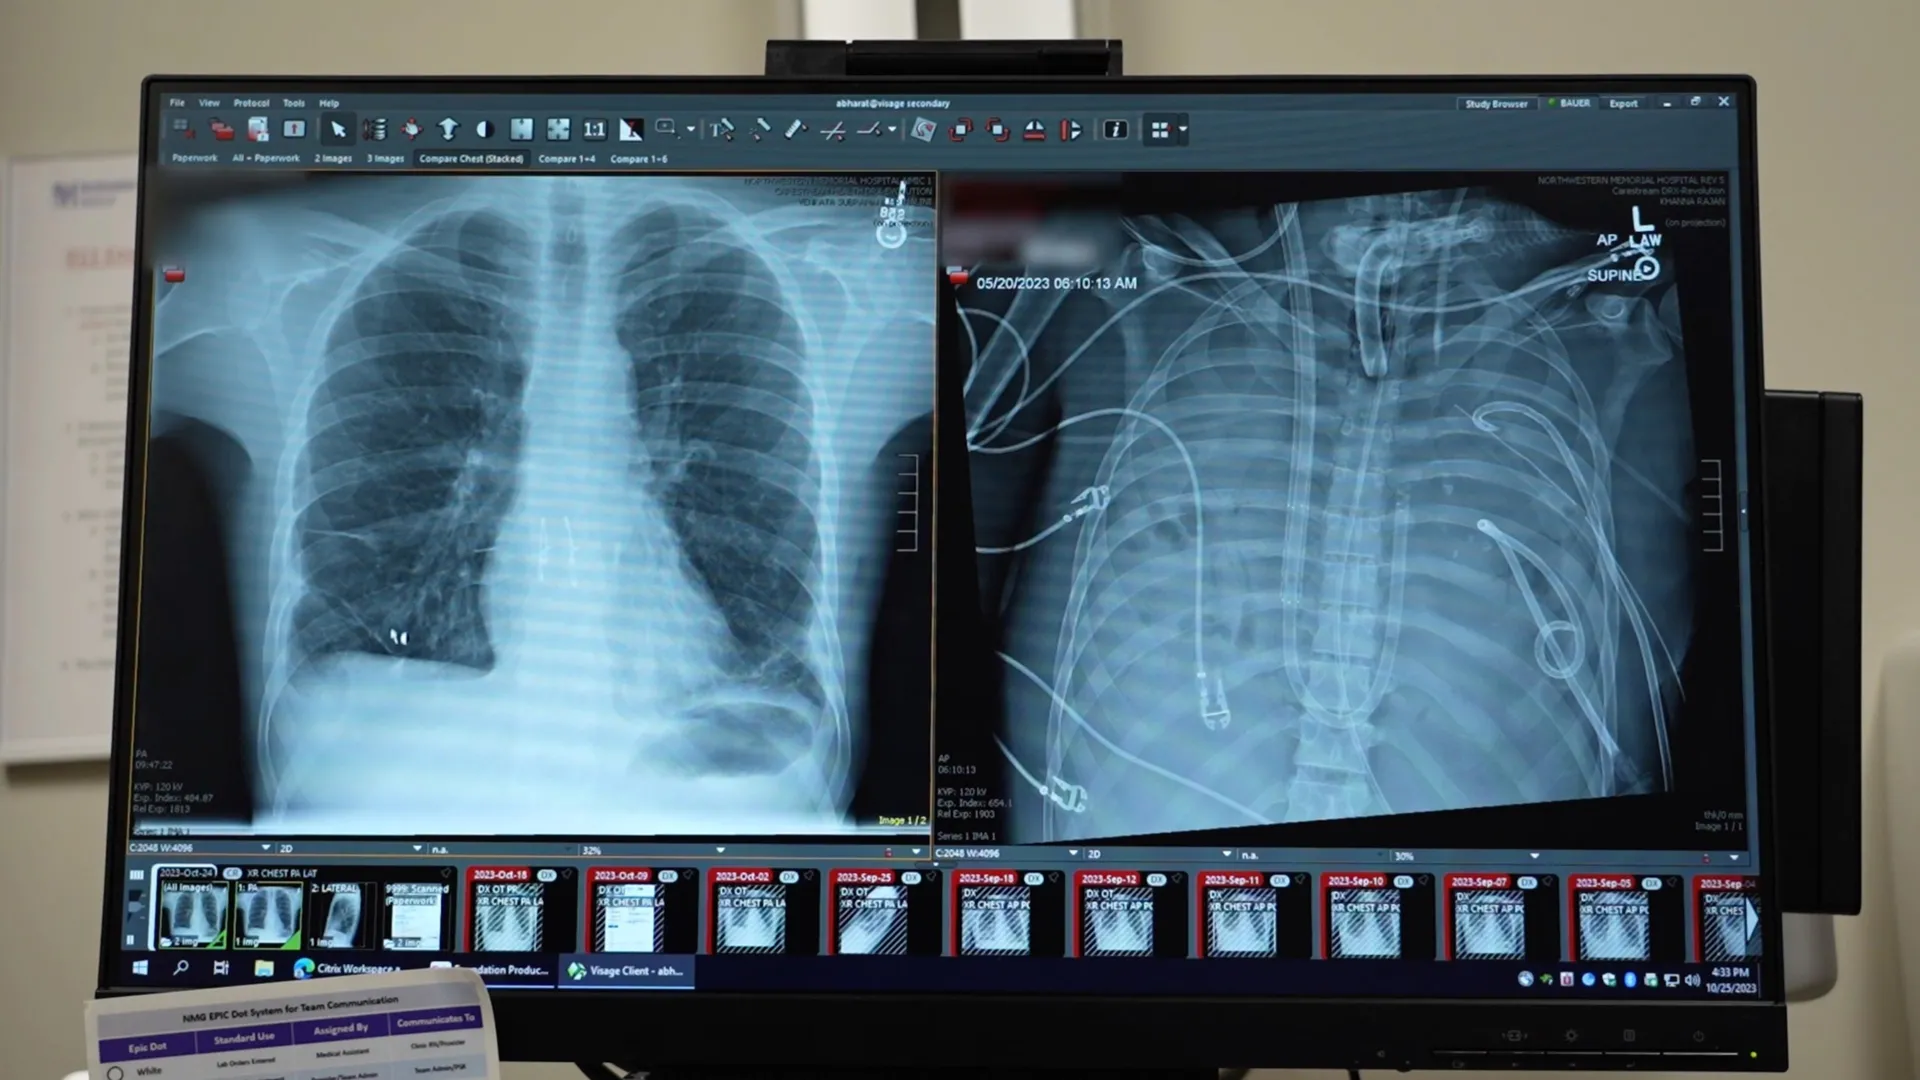

The patient, a 33-year-old male, presented with an alarmingly severe presentation of acute respiratory distress syndrome (ARDS), a life-threatening condition characterized by widespread inflammation and infection within the lungs, leading to profound respiratory compromise. His initial illness stemmed from a severe influenza infection, which rapidly deteriorated and became complicated by a secondary bacterial pneumonia. As his condition spiraled, his respiratory system, along with his cardiac and renal functions, began to fail catastrophically. At this critical juncture, a double lung transplant emerged as his sole viable option for survival, a procedure complicated by the extreme instability of his overall health.

The urgency of the situation was underscored by the patient’s arrival, during which his heart had stopped, necessitating immediate cardiopulmonary resuscitation (CPR). Lead author Ankit Bharat, a thoracic surgeon at Northwestern University, described the dire circumstances, explaining that when lung tissue becomes so ravaged by infection that it effectively "melts," the damage is irreversible, and survival is typically impossible. In this particular case, the severely infected lungs were not only non-functional but were actively propagating the infection throughout the patient’s body, posing an immediate and overwhelming threat. However, the patient’s precarious physiological state rendered him too unstable for an immediate transplant, creating a critical window where medical intervention was needed to stabilize him before the complex surgical procedure could be attempted.

The intricate connection between the heart and lungs presented a significant challenge: how to maintain circulation and oxygenation in the absence of the primary respiratory organs. To bridge this gap, the dedicated medical team devised and implemented an innovative artificial lung system. This ECMO configuration was meticulously engineered to assume the vital functions of the patient’s lungs. It expertly oxygenated the circulating blood, efficiently removed carbon dioxide, and provided crucial circulatory support, thereby enabling the patient’s heart and other vital organs to continue functioning adequately despite the complete absence of his native lungs.

Following the surgical removal of his critically diseased lungs, the patient’s clinical status began to show signs of stabilization and improvement. His blood pressure normalized, his failing organs started to recover, and the rampant infection was gradually brought under control. This period of critical stabilization, facilitated by the artificial lung, lasted for two days, during which time a suitable donor organ became available. Surgeons then proceeded with the complex double lung transplant, which was performed successfully. More than two years post-transplantation, the patient has made a full recovery and is living a normal life, demonstrating the profound efficacy of this integrated approach to critical care.